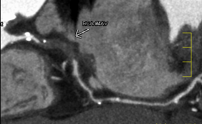

冠動脈狭窄症例